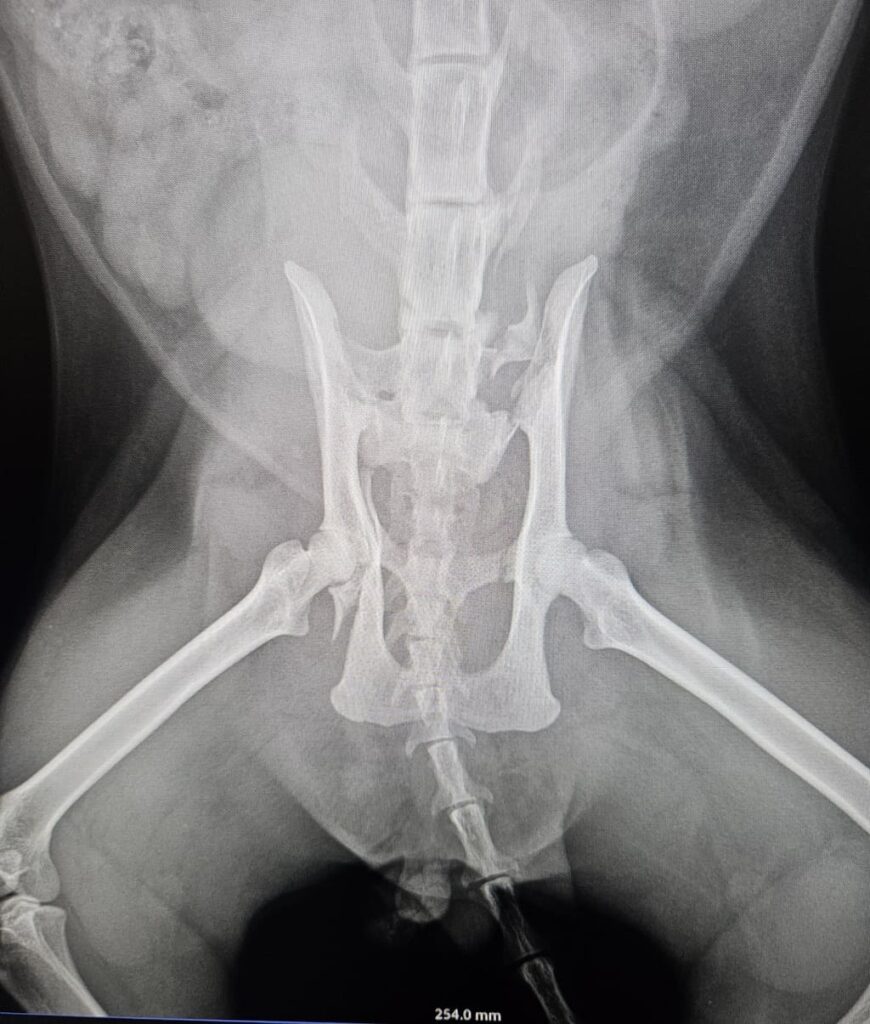

Le condizioni del povero micio

Il micio trovato investito e abbandonato in strada dovrà subire un intervento. Ha anche la vescica lacerata. Abbiamo bisogno di soldi, da soli non possiamo farcela, la cifra è alta.